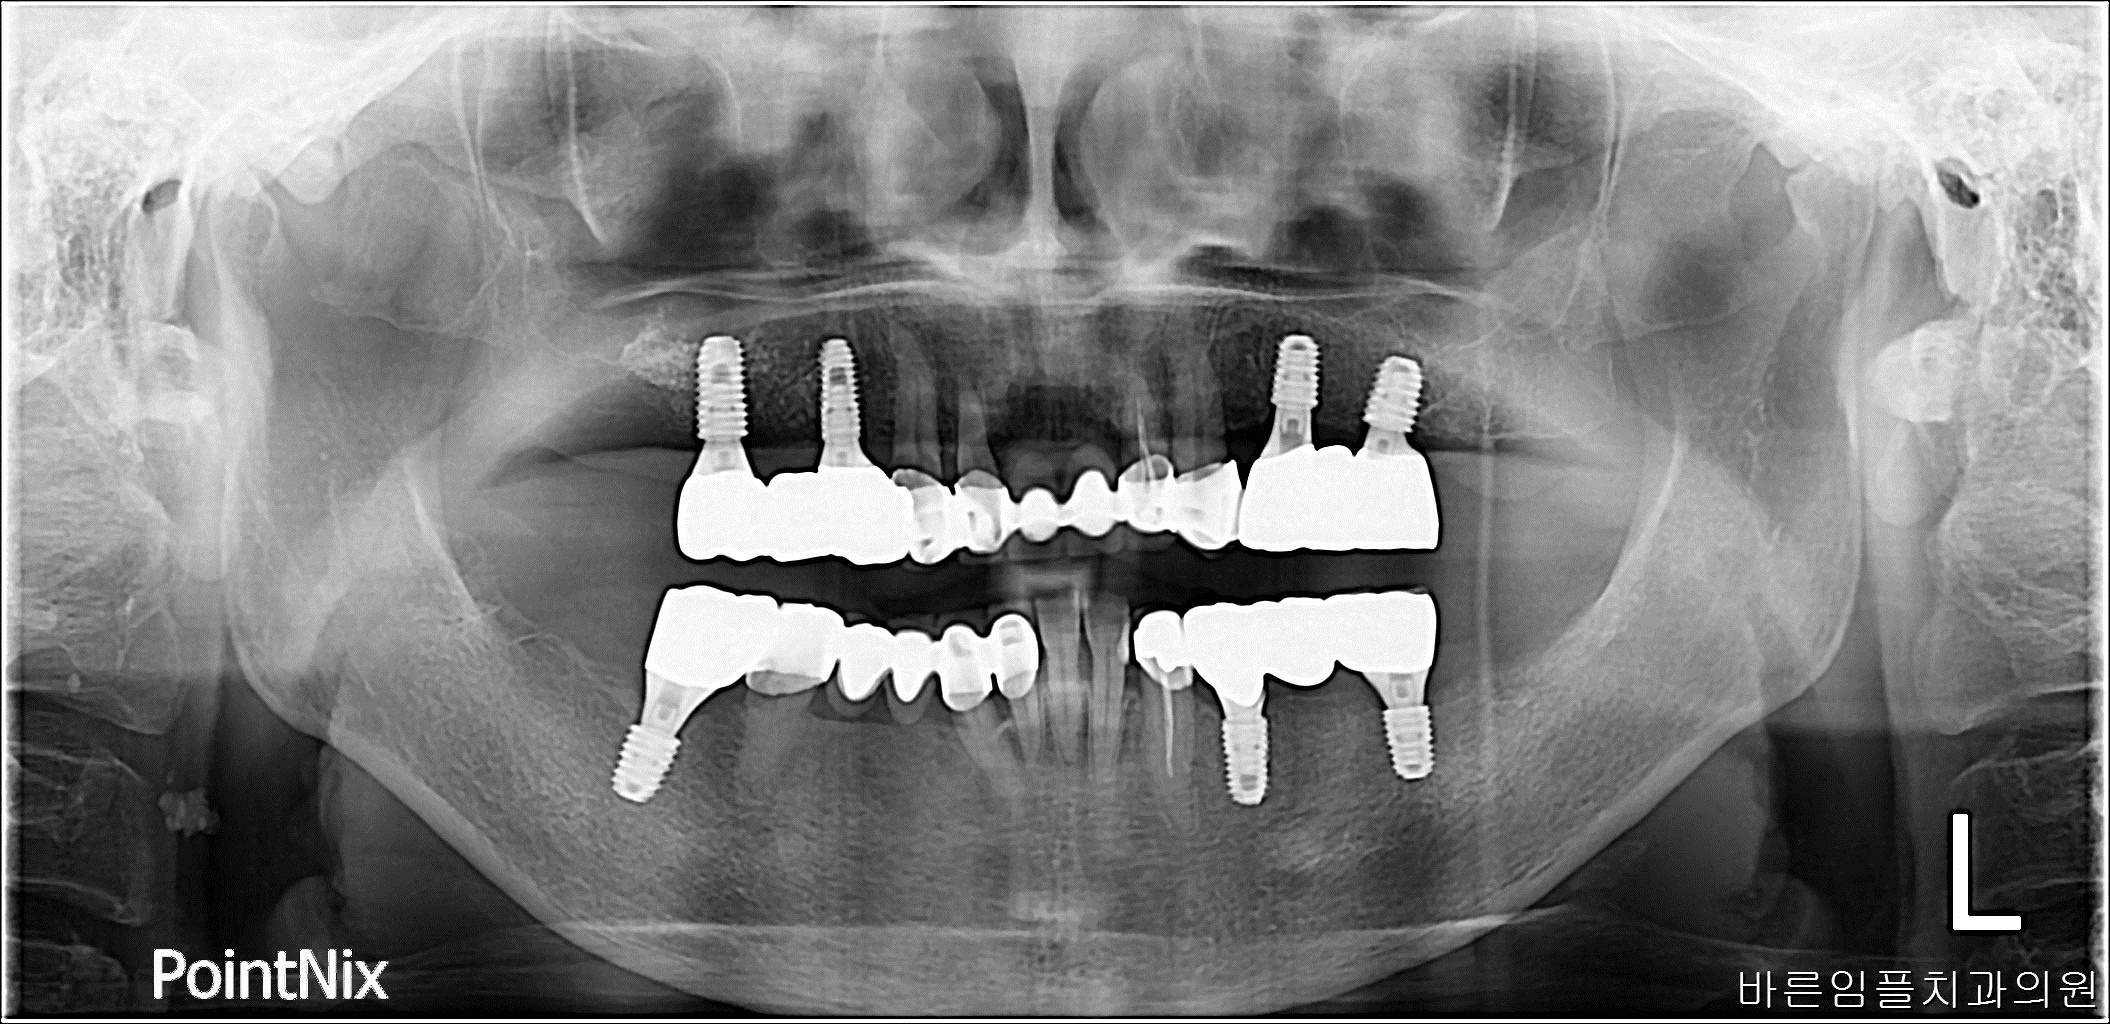

김ㅇㅇ / 수면임플란트 페이지 정보 작성일 23-10-27 16:57 2022-12-05 김ㅇㅇ Before 2023-07-04 김ㅇㅇ After 김ㅇㅇ / 수면임플란트 목록 이전글김ㅇㅇ / 임플란트 다음글 김ㅇㅇ / 임플란트